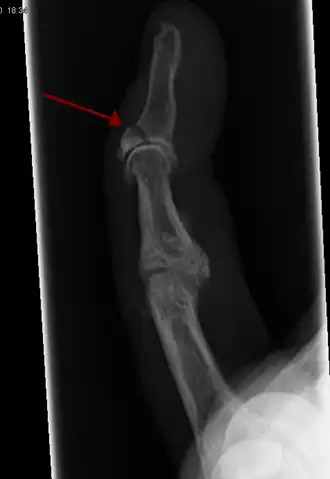

La radiografía que muestra fractura en la inserción del tendón extensor